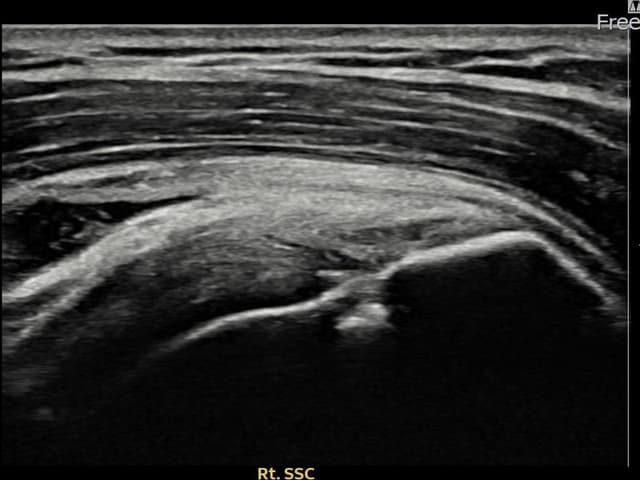

右侧 견갑하근건 关节面侧部分撕裂

7mm × 3mm (肌腱厚度约28%缺损)